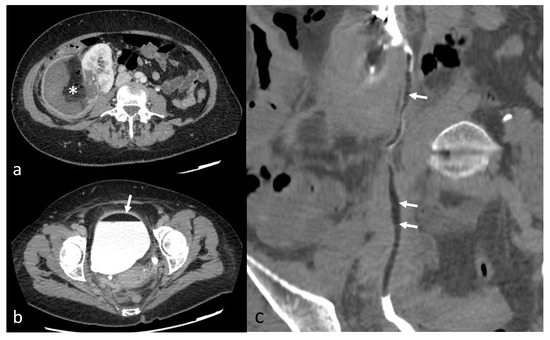

Figure 6.

Postembolization lipuria in a 70-year-old patient with a right AML. (a) Intratumoral necrosis (*) on axial computed tomography with injection and urinary acquisition (b) Fat-supernatant indicating lipuria (white arrow) on axial computed tomography with injection and urinary acquisition (c) Intra-ureteral fat (white arrows) on coronal computed tomography with injection and urinary acquisition.

Minor complications were recorded in three patients (12%) and major complications in two patients (8%). One patient had a non-targeted embolization of the renal parenchyma during embolization (minor complication). The Onyx was not correctly visible (on poor homogenization with tantalum powder). The non-target embolization represented 28% of renal parenchyma, with no alteration of renal function at follow-up. One other patient had a pseudoaneurysm of the punctured femoral artery resulting in an additional day of hospitalization (minor complication). Doppler follow-up showed the resolution of the latter after being successfully treated by ultrasound-guided compression and monitoring. One patient had a post-embolization syndrome (PES) 48 h after embolization, with further anti-inflammatory and analgesic treatment (minor complication). One patient had a renal artery dissection during embolization, ultimately leading to non-target embolization of 20% of the kidney (major complication). The patient then had a pulmonary embolism and the appearance of a bilateral pleural effusion. She presented with hypovolemic shock due to a massive retroperitoneal rupture of the tumor. She also developed healthcare-associated pyelonephritis (major complication). One other patient presented, 15 days after embolization, a superinfection of the embolization site with fistulization in the pyelocaliceal system, leading to lipuria (Figure 6). The patient was hospitalized with antibiotics and analgesics (major complication). The AML drained itself almost completely into the pyelocaliceal cavities, conducting a volume shrinkage of 99%.